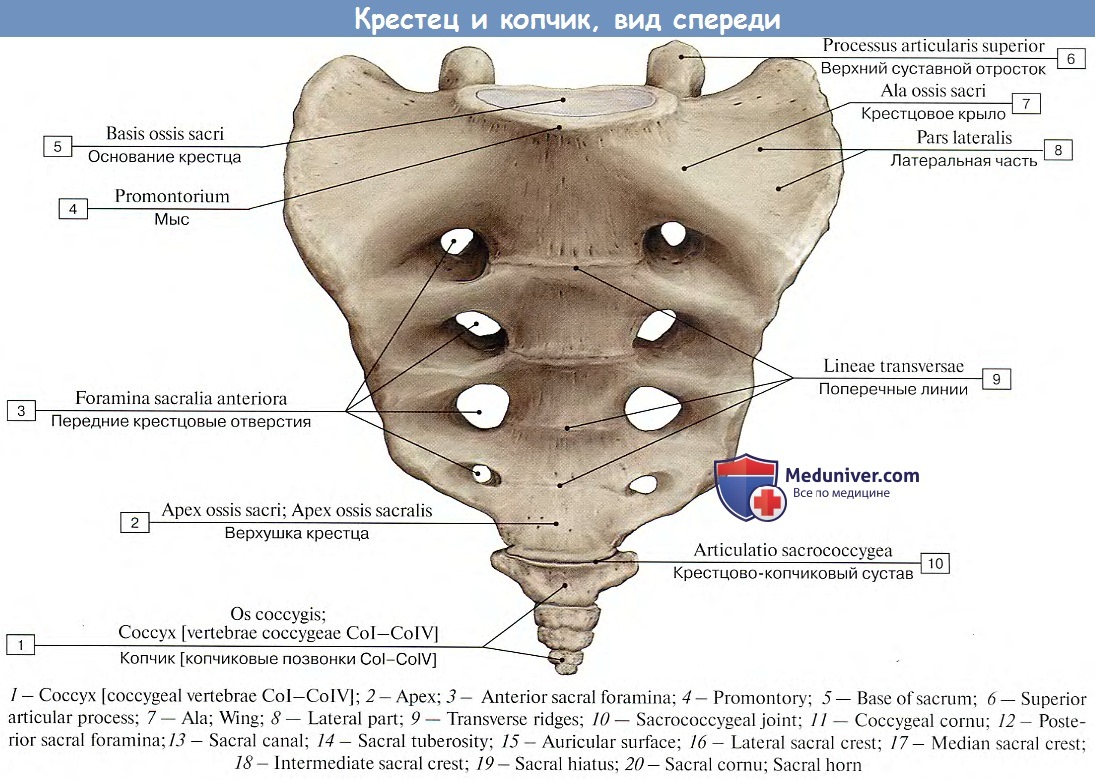

Структура позвоночника: сегменты и тазовые отделы в фотографиях